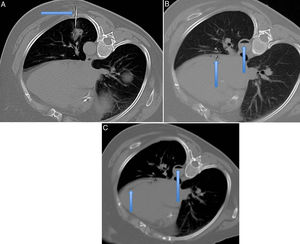

Cortes axiales de la TC para la realización de una biopsia pulmonar con la paciente colocada en decúbito lateral derecho. A) En la imagen superior izquierda se puede ver señalada la aguja tru-cut abordando la lesión alojada en el lóbulo inferior izquierdo (flecha). B) La imagen superior derecha muestra, señalado por flechas, la existencia de aire dentro de la arteria aorta descendente (flecha) y en la arteria circunfleja (flecha). C) En la imagen inferior se demuestra la existencia de aire en el interior del ventrículo izquierdo (flecha).

Inmediatamente tras la pospunción comienza con tos y esputos hemáticos rojo vivo, con cuadro de sudoración, dolor torácico y dificultad respiratoria manteniendo saturaciones del 96%. En la TC existe mínimo neumotórax y aire en la aorta torácica descendente y en la arteria circunfleja (fig. 1B).

Minutos después mejora clínicamente; se realiza nueva TC en la que ha disminuido el aire en la aorta descendente y existe mínima cantidad en el ventrículo izquierdo (fig. 1C).